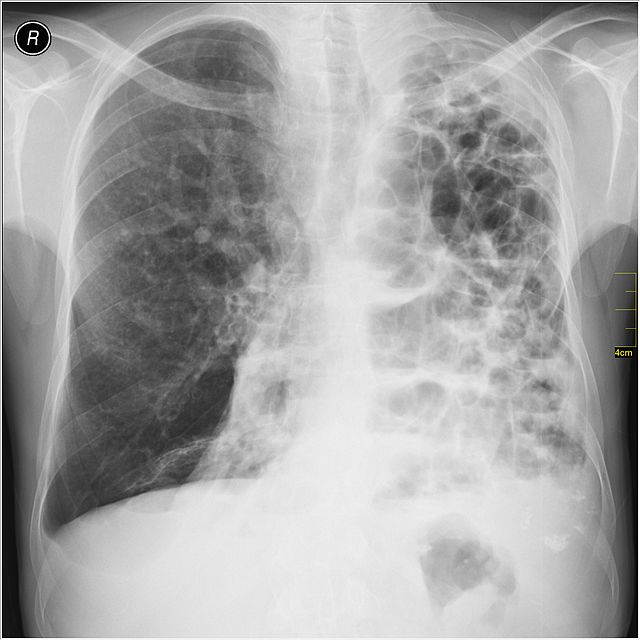

Рентгеновские снимки при врожденной эмфиземе легкого

Раздел: Визуальные уроки